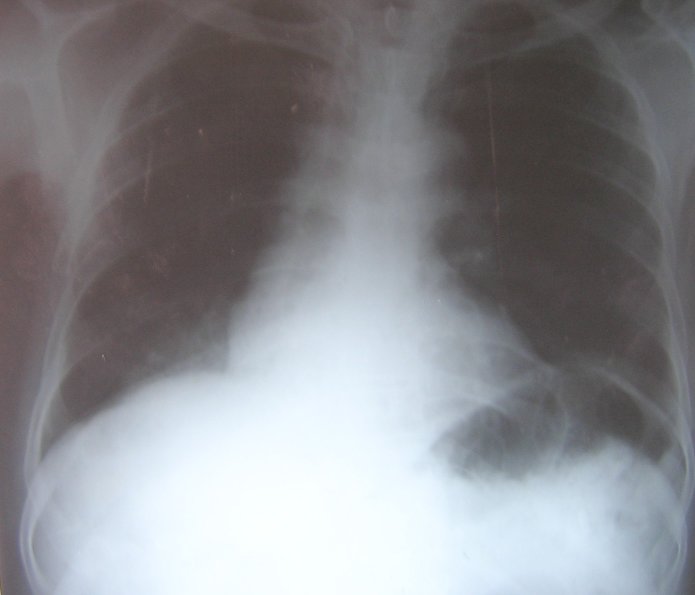

A computerized tomography (CT) scan ofthethorax (figure 6) showed consolidation in the right lower lobe. There was no hilar or mediastinal lymphadenopathy or narrowing of the right lower lobe bronchus.

Figure 6: CT scan of the thorax showing air bronchogram in the right lower lobe